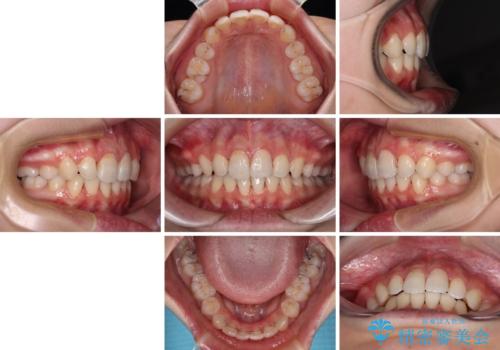

指が入るくらいに隙間のある上下前歯 抜歯矯正で横顔の印象が大きく改善

高校生ということもあり、治療期間は2年を切るスピードでした。

舌の突出癖は十分に改善されたとは言えない状態でしたので、今後の後戻り防止対策として、経過観察中も舌のトレーニング指導を行っていくこととなります。